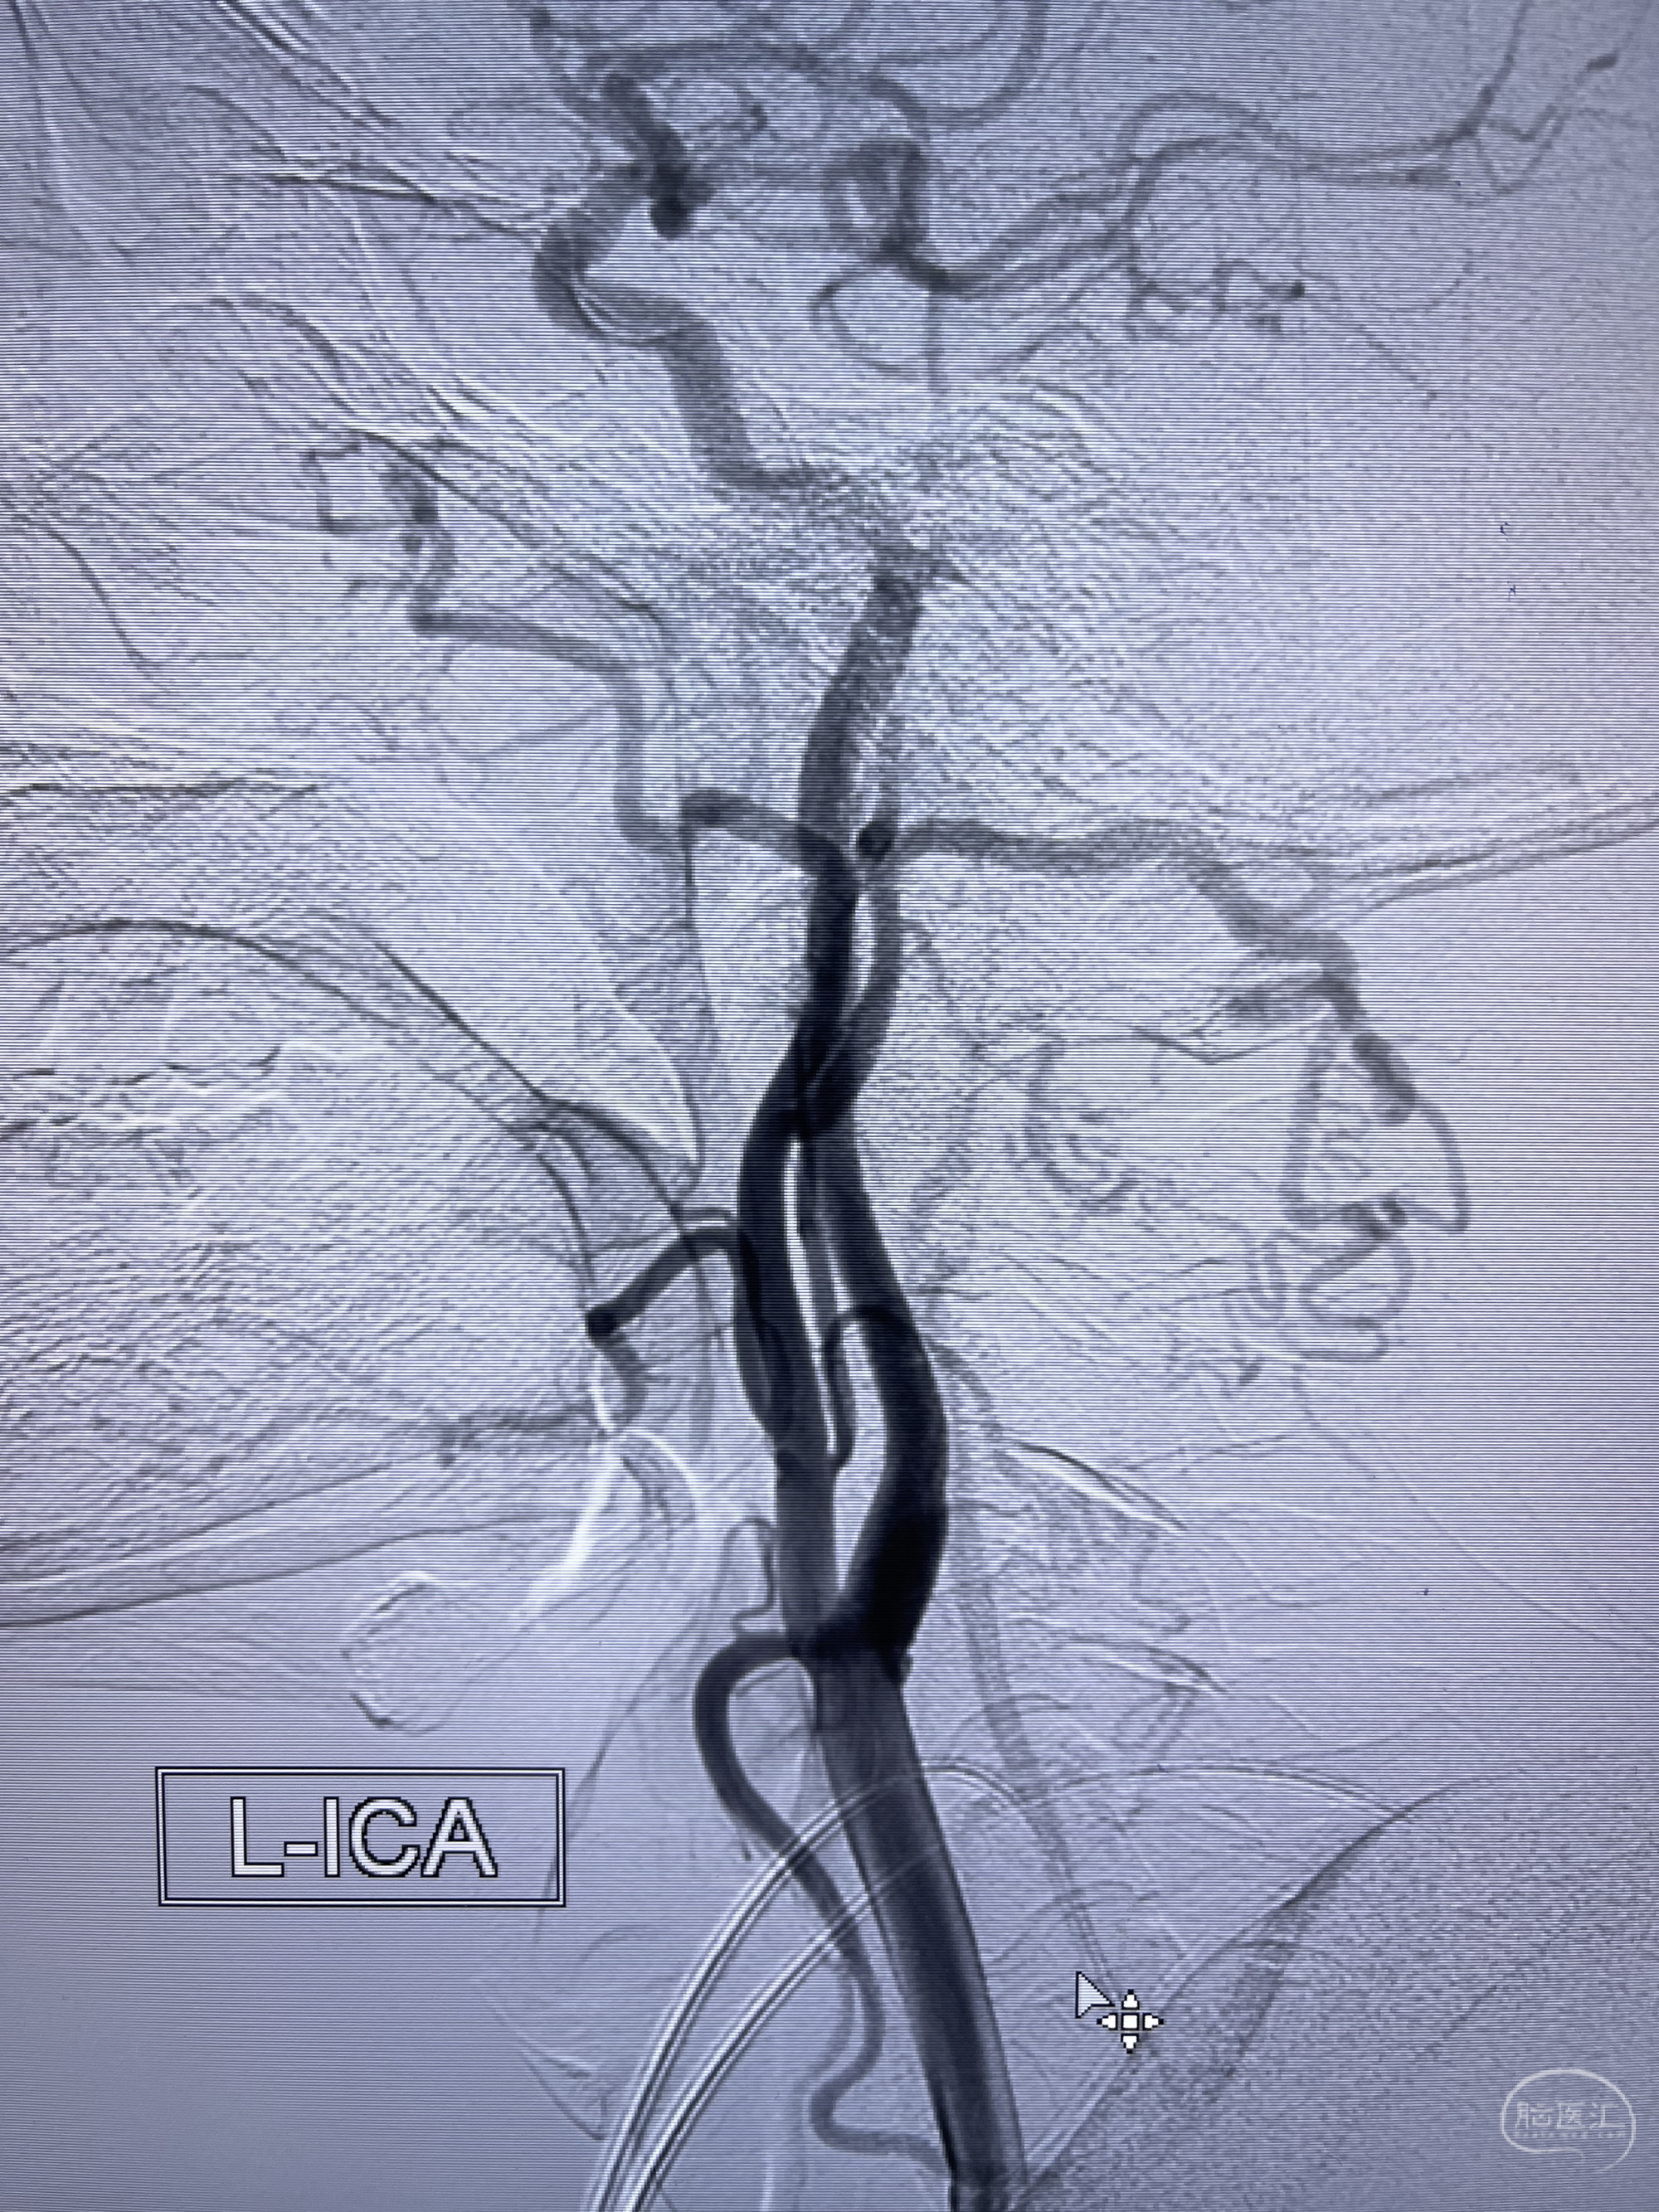

脑血管造影2023.03.06:右侧颈内动脉颈段至岩骨段闭塞,可见后后循环通过原始三叉动脉吻合代偿至海绵窦段,后交通区可见囊状造影剂填充影,左侧锁骨下动脉呈“残端”改变,呈“右侧颈总动脉支架成形术后改变”,支架内血流通畅,可见后交通吻合显影至左侧大脑后动脉,并可见左枕动脉吻合椎动脉至锁骨下动脉

2023-03-06DSA:

5.左侧颈总动脉起始部支架术后

6.左侧颈外动脉可见吻合显影至左侧椎动脉并逆行供血至左侧腋动脉

7.左侧锁骨下动脉闭塞